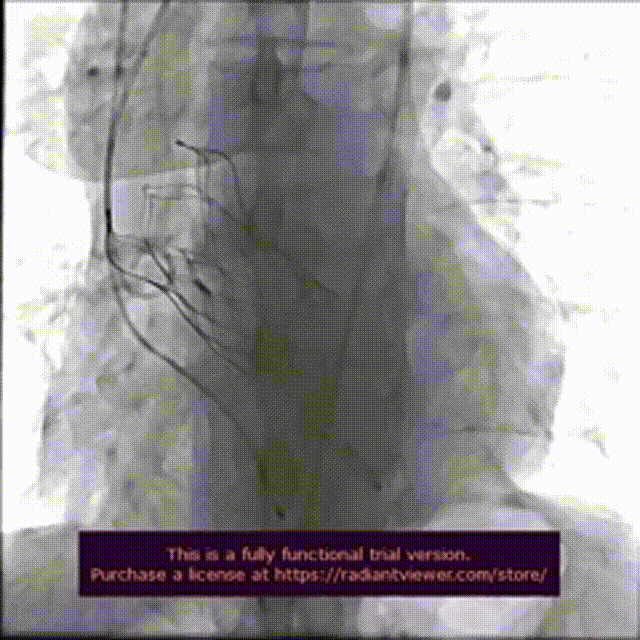

手术过程:

术前造影检查,主动脉瓣大量返流

圈套器辅助下,送入30mmVitaflow瓣膜

造影定位,可见无冠瓣叶较高

快速起搏条件下前期释放2/3瓣膜

造影显示瓣膜位置良好后完全释放

术后造影

数字减影模式检查下肢血管